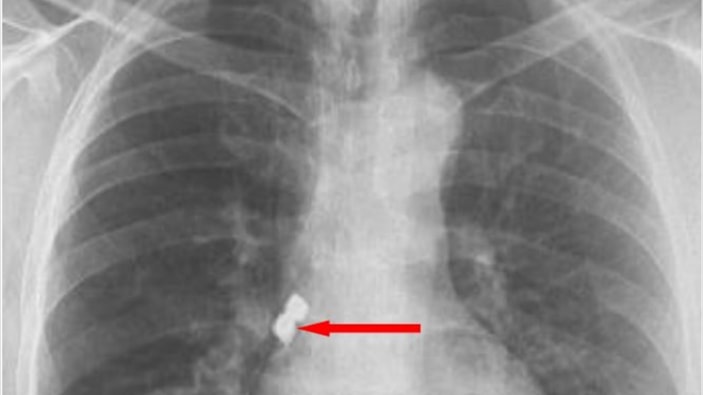

Operasyon sırasında birbirine yapışık olan 2 implant hastanın dişinden düştü.

Kaplan, yutkununca implantlar soluk borusuna kaçarak burayı tıkadı.

Kaplan'ın akciğer girişinden implantlar başarıyla çıkarıldı.